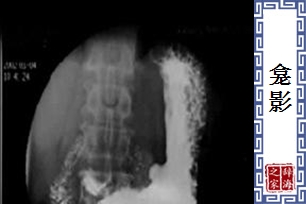

- 检查胃肠时,先饮下钡餐,以填充胃肠的溃疡部位,此时在萤光屏或X光照片上所形成的阴影,即称为「龛影」。

【龛影】 图片鉴赏